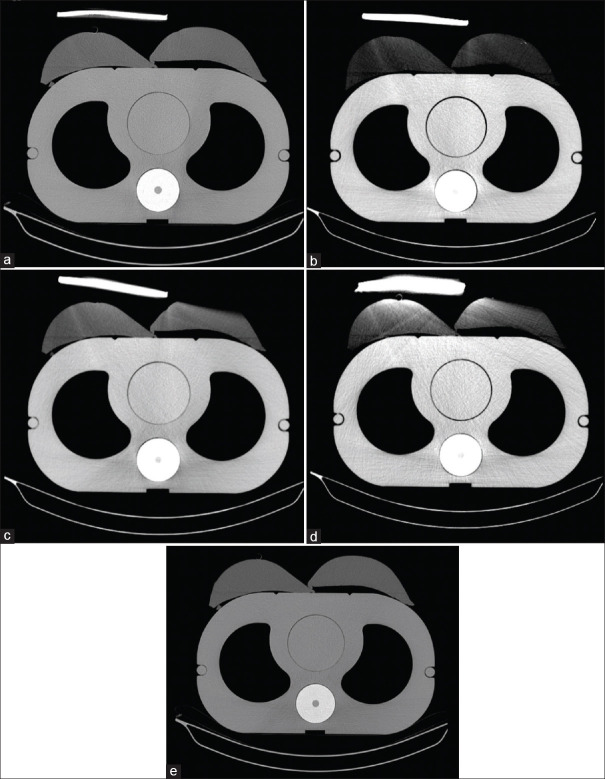

Methods: Four breast shields were fabricated: one with 10% bismuth and three with 10%, 15%, and 20% BaSO4. Dose reduction was assessed using a thorax phantom and ionization chamber. Image quality effects were evaluated in the thorax phantom by measuring noise and CT number changes. The 10% barium shield was further tested on 22 patients undergoing chest CT.

Results: The 10%, 15%, and 20% barium shields reduced breast dose by 36.8%, 38.6%, and 45.6%, respectively, while the 10% bismuth shield achieved a 63.1% reduction. However, the 10% barium shield had minimal impact on image quality, increasing lung noise by only 0.3 Hounsfield units (HU) and shifting CT numbers by 4.7 HU. In patient studies, 81.8% of scans showed no artifacts, with 18.2% showing slight artifacts.